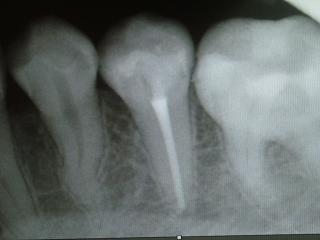

レントゲンにて確認。

「ピタッと根充」を目指します。

根管治療(歯内療法)の症例